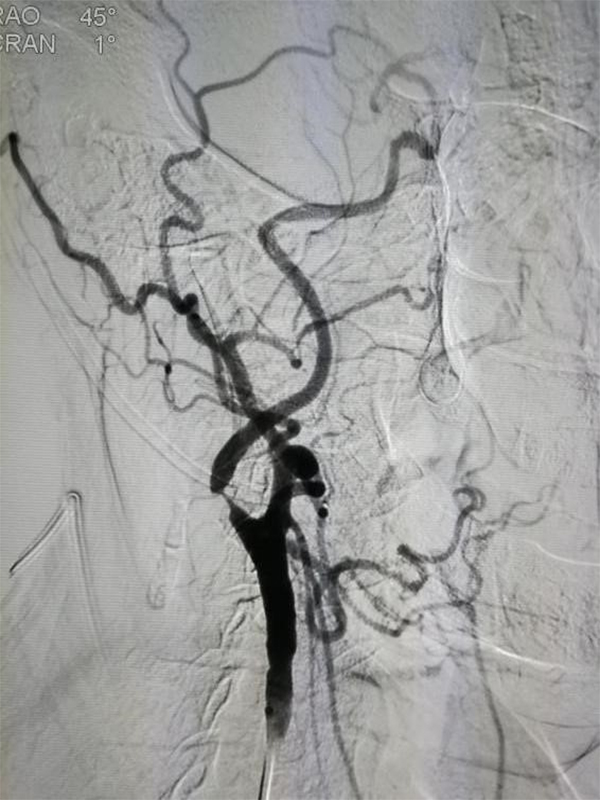

MRA CTA (CT ) DSA <50 %) MRA 50 % CTA 80% DSA 99 % ( ) CTA DSA

CTA 100 % 63 %(95 % 25 %-88 %) 70 % 100 %

NASCET 1 % MRA CTA